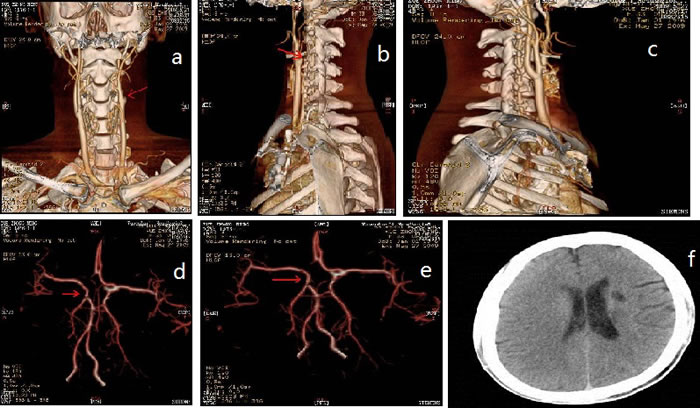

Figure 1: CT-angiography and brain magnetic resonance imaging (MRI). Red arrows: multifocal infarction

Splenomegaly, gynecomastia and enlarged axillary lymph nodes were confirmed by sonography. CT-angiography disclosed occlusion of the left internal carotid artery and disappearance of the left intra-cranial internal carotid artery (Figure 1). Brain magnetic resonance imaging (MRI) showed multifocal infarction beside the left lateral ventricle (Figure 1). A skeletal radiographic survey and computed tomography (CT) scan revealed multifocal sclerotic bone lesions in the thoracolumbar vertebrae and pelvis (Figure 2). On neurologic examination and nerve conduction studies, distal sensorimotor polyneuropathies were noted in his limbs. Bone marrow aspirate and biopsy gave no evidence of plasma-cell dyscrasia, and Bence Jones protein was negative in the urine. Immunofixation electrophoresis test did not detect monoclonal protein in the serum and urine for the first time. One week later, however, we repeated the serum protein and immunofixation electrophoresis in another laboratory and this time the presence of monoclonal protein (λ-light chain in the γ region ) was detected (Figure 3).